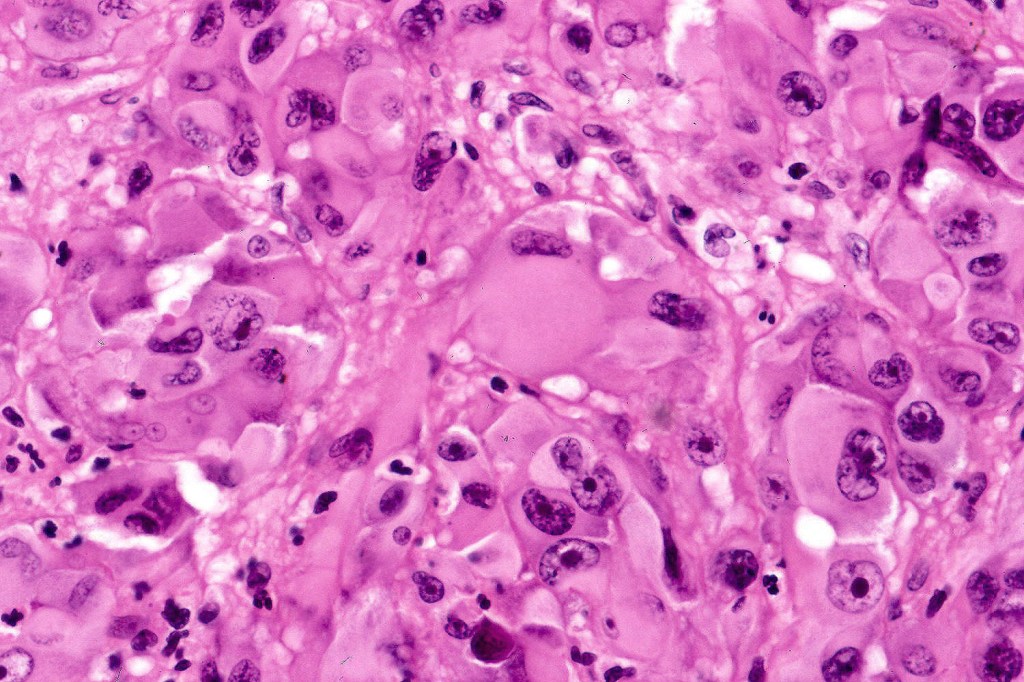

•Immunophenotype is variable with possible loss of expression of one or more of the usual melanocytic markers including S100 & SOX10 (occasionally), HMB45/MART-1 (not uncommon), MITF & tyrosinase

•A broad panel is recommended to detect positivity in one or more of these markers

•Loss of INI1 expression described

In this example, rhabdoid change accounted for only a small component of the tumor. IHC is S100